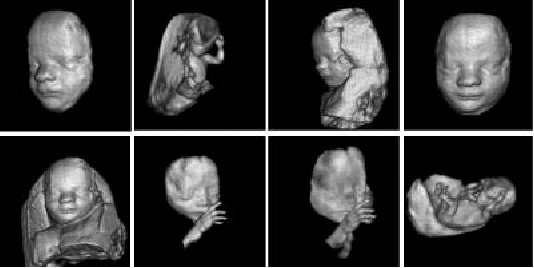

The ultrasound that we have described so far presents a two dimensional image, or "slice," of a three dimensional object (foetus, organ). Two other types of ultrasound are currently in use - 3D ultrasound imaging and Doppler ultrasound. Several two-dimensional images are acquired by moving the probes across the body surface or rotating inserted probes. The two-dimensional scans are then combined by specialized computer software to form 3D images, shown below.

3D imaging allows you to get a better look at the organ being examined and is best used for:

Visualizing a foetus to assess its development, especially for observing abnormal development of the face and limbs

Visualizing blood flow in various organs or a foetus